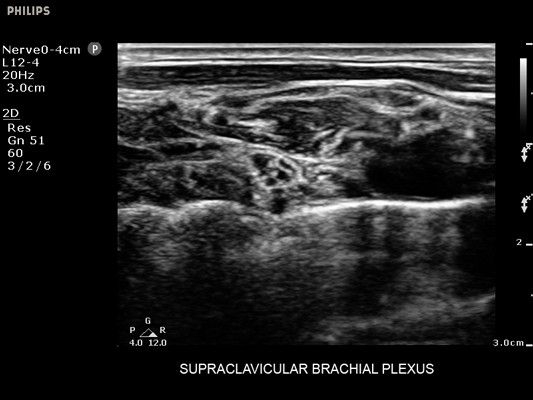

• Усиленная визуализация иглы без потери качества изображения окружающих тканей

• Метки центральной линии на датчиках L12-4 и C6-2 для упрощения внеплоскостной навигации

• Диагностика нервов

• Линейный УЗИ датчик Philips L12-4